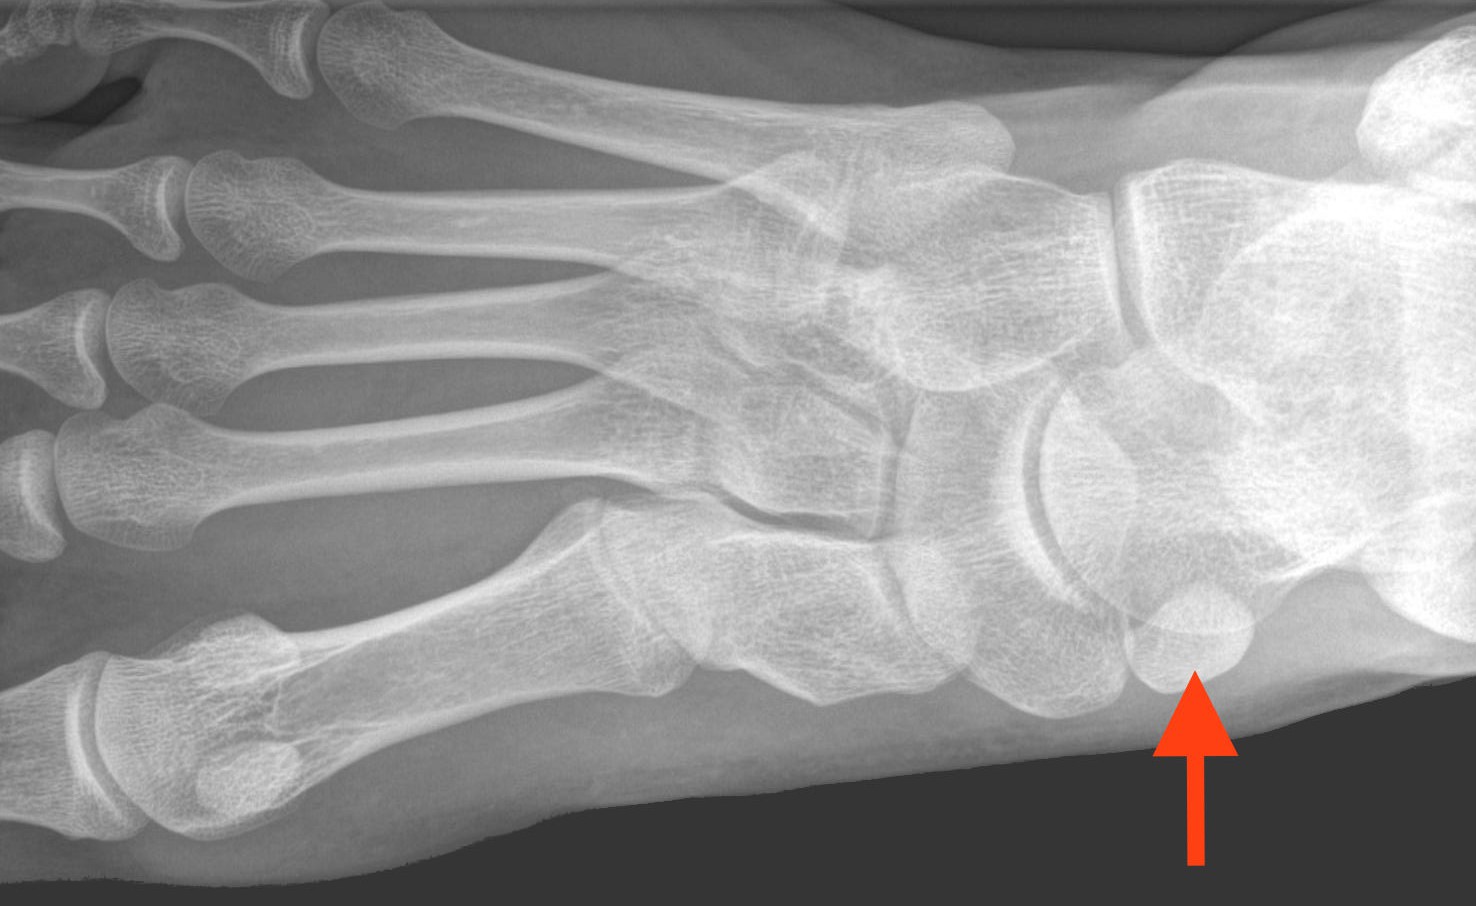

The next extra bone in the foot that is a source of discomfort is located on the other side of the os naviculare, which I discussed last post. The os peroneum is located on the outer side of the foot, near the middle of the foot’s length. This round to oval shaped bone is found either under or within the dual tendons of the peroneal muscles. These tendons help the peroneal muscles pull the foot outward, and they also act as a stabilizer for the foot when walking on uneven terrain. It is not uncommon for one or both of these tendons to become injured and inflamed. The os peroneum can also contribute to this injury by irritating the overlying tendon. Tight shoes can further this irritation, as can direct impact against the side of the foot.

Interestingly, this bone is sometimes mistaken for a fracture fragment in emergency rooms, especially if it is a little more jagged in appearance and lies close to the base of the 5th metatarsal bone, a long bone in the side of the foot that has a part which flares out into the side of the foot.